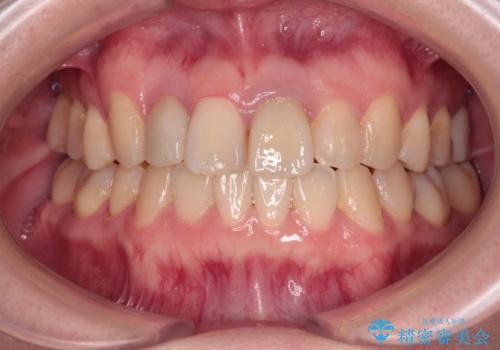

デコボコと口元の突出感を改善 抜歯矯正治療

患者様には辛抱強く治療にお付き合いいただき、すっきりとした口元に仕上げることができました。